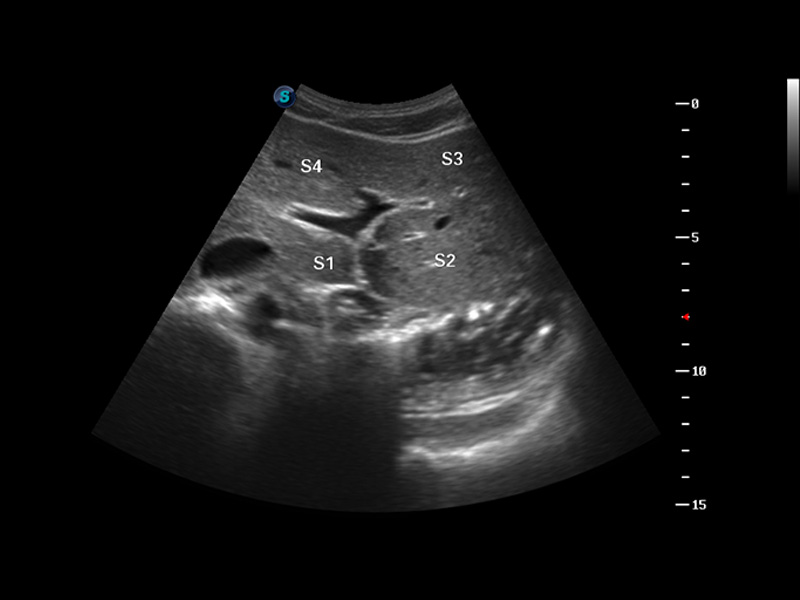

谐波成像

空间复合成像